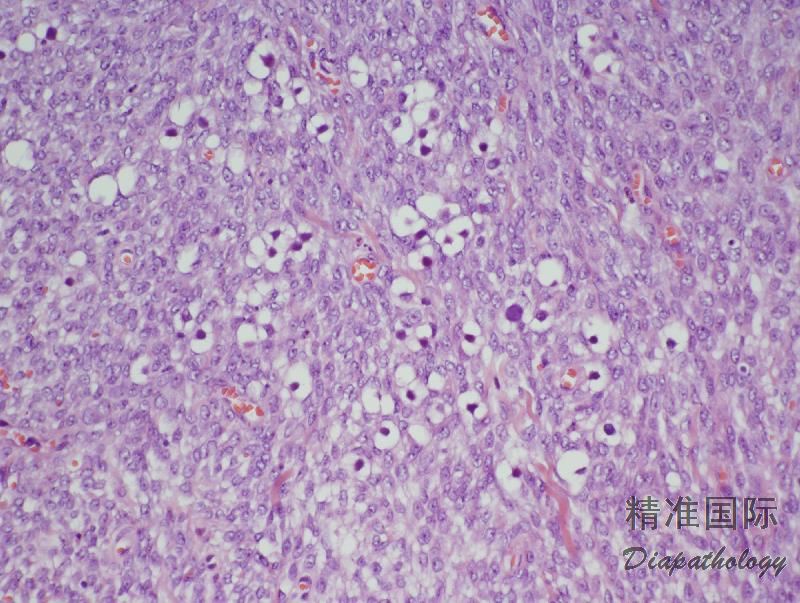

性索-间质肿瘤,具两种或两种以上性索-间质肿瘤成分。

- 由两种或两种以上性索-间质肿瘤成分构成,各成分比例不定,混合方式不一;

- 偶尔可见正常结构的曲细精管陷入肿瘤中。